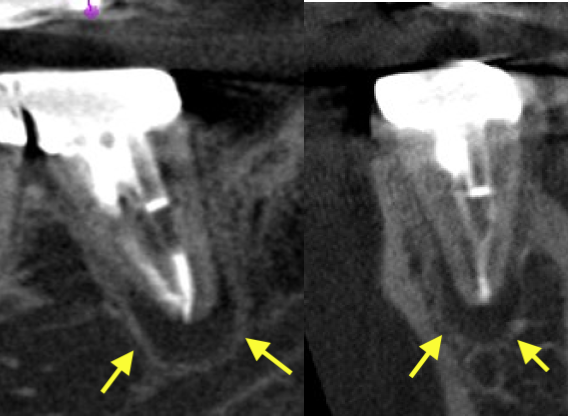

• 歯根端切除前と術後半年のCBCT画像、感染源を除去してしっかり封鎖したことで、骨の再生を認め治癒が確認されました(黄色矢印)。

• 意図的再植術 術前CBCT

左下第二大臼歯、術前のCBCT画像で根の周りに透過像(炎症の黒い影、黄色矢印)があり、腫れの原因となっていることがわかる。根管充填は根尖まで届いていいる。Csahepのため根管治療で殺菌が届かないところが原因となると、同じことをくりかえしても効果がない可能性も高い。ファイバーポストも深い位置まで挿入されているため除去に伴うリスクもある。カウンセリングの結果、より確実な方法で費用対効果の高い意図的再植術を行うこととなった。